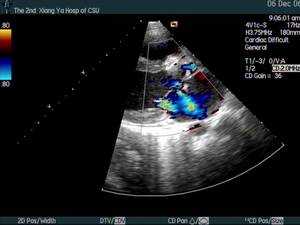

5、超聲心動圖心瓣膜或心內膜壁有贅生物,及固有心臟病的異常表現。